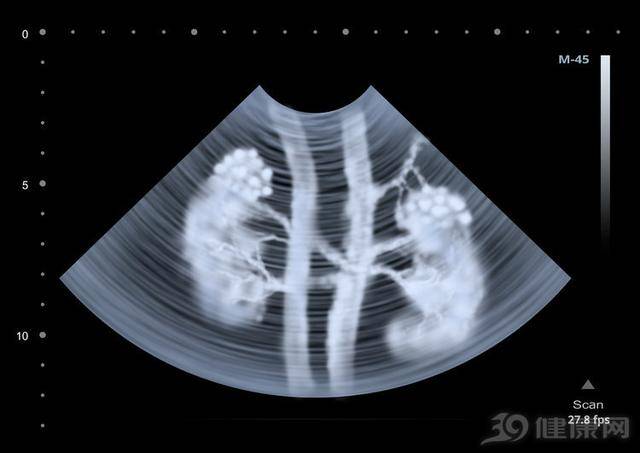

文章图片